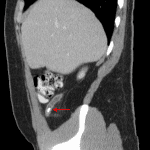

Age: 19

Sex: Male

Indication: Abdominal pain

Findings

- 7 mm calcific density overlies the right lower quadrant

Diagnosis

- Appendicolith

7 mm calcific density overlies the right lower quadrant, which though nonspecific could represent an appendicolith. Consider CT for further evaluation.